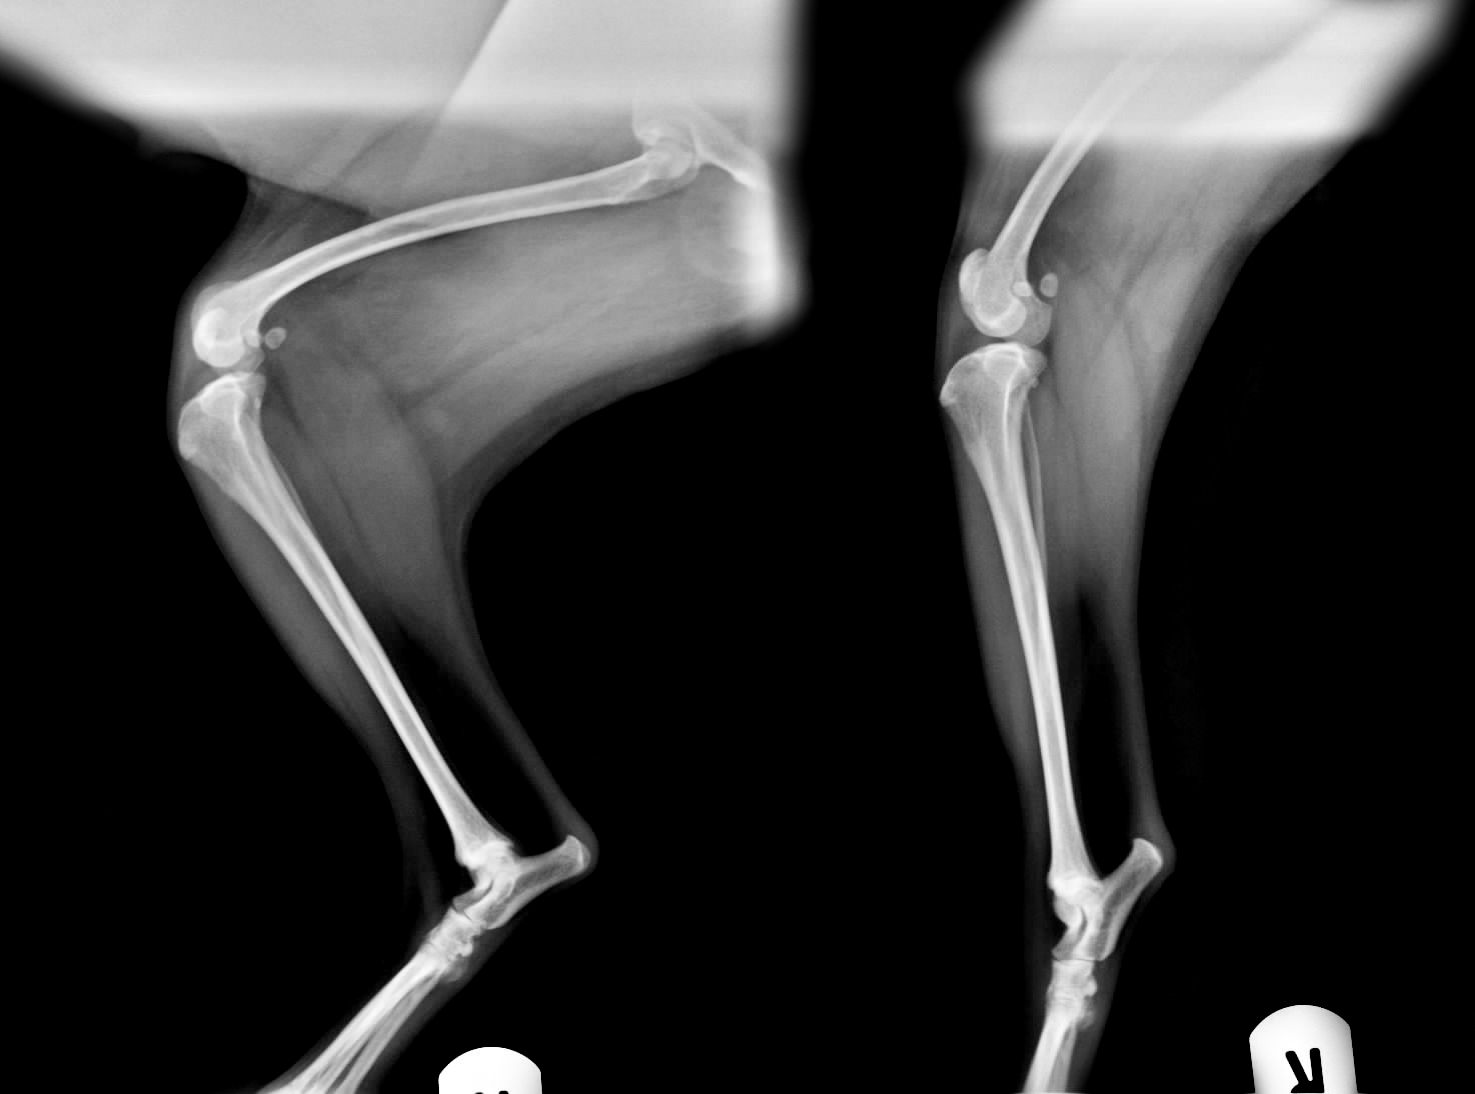

WebGrado I. Luxación de rótula intermitente, causando cojera de la extremidad solo cuando está fuera de su sitio. Son perros que cada tres o cuatro pasos levantan la. WebPara confirmar la sospecha de luxación patelar en perros, el veterinario palpará la rodilla cuidadosamente. Además, comprobará en qué medida y en qué dirección se luxa la. WebUna luxación rotuliana en perros es una de las anomalías más frecuentes de la articulación de la rodilla en los perros. La condición es más común en razas de perros de juguete y. WebEjercicios Para Luxación De Rótula En Perros Hola y gracias por visitar nuestro blog. En este artículo hablaremos de un producto de mucha calidad y muy buscado en tiendas en. WebClasificación de la luxación de rótula en perro. Existen varios sistemas de clasificación de la severidad de la luxación, pero el más usado por los clínicos es el de Roush, que.

WebUna luxación rotuliana en perros es una de las anomalías más frecuentes de la articulación de la rodilla en los perros. La condición es más común en razas de perros de juguete y. WebEjercicios Para Luxación De Rótula En Perros Hola y gracias por visitar nuestro blog. En este artículo hablaremos de un producto de mucha calidad y muy buscado en tiendas en. WebClasificación de la luxación de rótula en perro. Existen varios sistemas de clasificación de la severidad de la luxación, pero el más usado por los clínicos es el de Roush, que. WebA continuación apretaremos la pelota con ambas rodillas, intentando que las dos piernas hagan la misma fuerza. Elevar pierna inferior: nos colocaremos. WebShow more. 🦴LUXACIÓN DE RÓTULA EN PERROS Hoy os hablamos de la LUXACIÓN DE RÓTULA en perros y os contamos el caso de Lupe, esta YorkShire que padecía un. WebLa operación de luxación de rotula para perros significa conseguir que el hueso no duela al perro y pueda caminar y correr sin problemas. Se trata de la reconstrucción del hueso y. WebEn la situacion de las rodillas, existen varios ejercicios que se tienen la posibilidad de llevar a cabo, pero los más destacados son: Los paseos acuáticos asisten a recobrar la. WebLa otra rotula nunca le ha quedado al 100% y sigue casi igual de coja que antes d la operacion. Esta perra tuvo cachorros (yo no sabia que eso se heredaba) y uno de ellos. WebMasoterapia para perros con luxación de rótula. La terapia de masaje y el ejercicio correctivo pueden beneficiar a los perros con luxación leve de rótula. El.